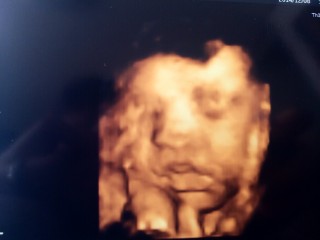

なかなか見れない週数に入りお顔を久々に見せてくれました!! 大きさは1860g程度、平均の大きさの女の子です。前回よりもお肉がついて赤ちゃんらしくなってきました。厚ぼったい唇は私に似ています。 目鼻立ちもしっかりしていると言われました!早く会いたくて仕方ないです。